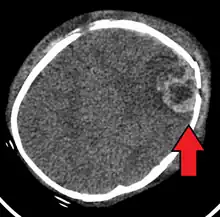

| An intraparenchymal bleed with overlying skull fracture from shaken baby syndrome | |

A skull fracture from abusive head trauma in an infant A skull fracture from abusive head trauma in an infant